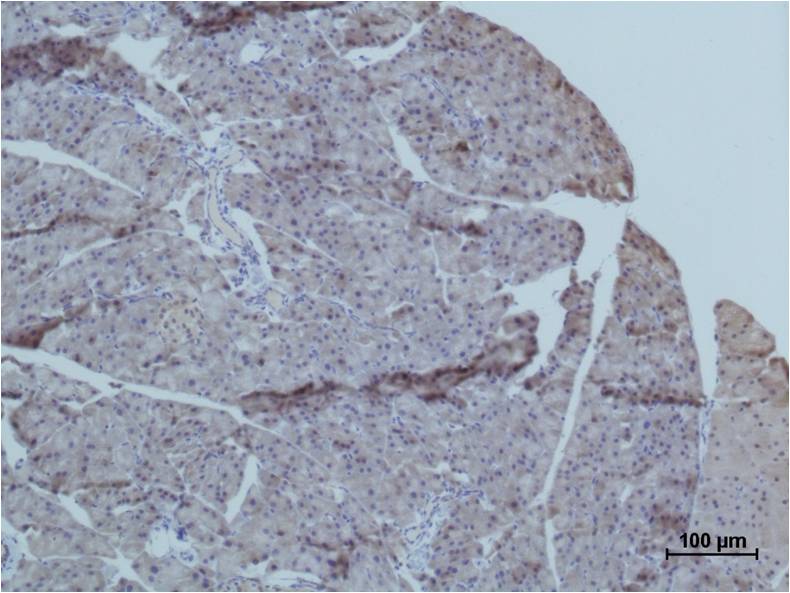

Product name: TRIM72/MG53 Rabbit pAb

Dilutions: WB 1:1,000? IHC 1:200-500